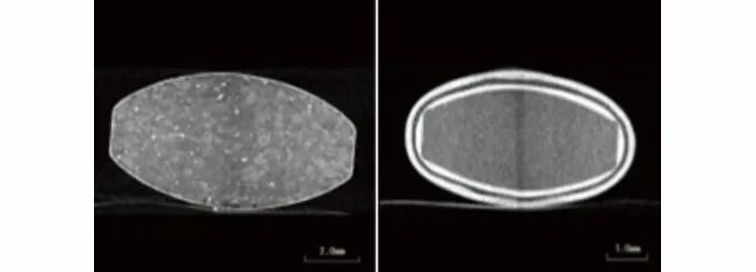

图4片剂A的CT效果图(左)图5片剂B的CT效果图(右)

在本例中,观察到两种具有不同结构的片剂(片剂A和B)(图2)。片剂的透视图像如图3所示。

本例描述了使用inspeXio SMX-90CT Plus台式微焦点X射线CT系统(图1)分析两种药片。

使用XRAY透视和CT 扫描,对其内部进行扫描和分析。

除了不需要任何特殊的预处理,X射线CT检查系统允许在不损坏样品的情况下获得内部信息。因此,它们可用于三维观察和分析药物层的分布状态或厚度。